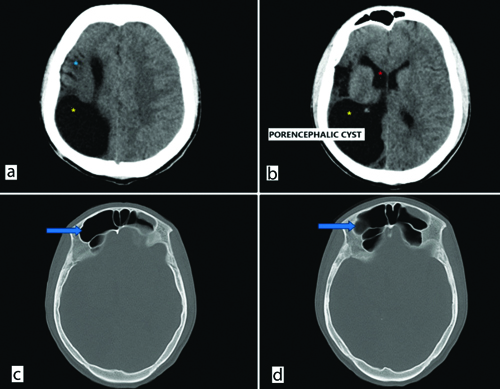

On Computed Tomography (CT) scan [Table/Fig-3a-d], gliotic changes in the right parietal lobe were observed, along with right-sided cerebral atrophy and ex-vacuo dilatation of the frontal horn of the right lateral ventricle. A large porencephalic cyst was present, involving the right parieto-temporo-occipital region and communicating with the right lateral ventricle. Hyperpneumatisation of the bilateral frontal sinuses was noted, more on the right side, with marginal thickening of the bony calvaria. The co-existence of DDMS and a porencephalic cyst sets this patient’s case apart. As there were no cutaneous manifestations or intracranial lipoma, Fishman syndrome was ruled out [2].

a and b) Non contrast Computed Tomography (NCCT) brain axial image demonstrates gliotic volume loss in right parietal region (blue asterisk), dilatation of frontal horn of right lateral ventricle (red asterisk) and a large porencephalic cyst (yellow asterisk) communicating with right lateral ventricle (internal type); c and d) Hyper pneumatisation of bilateral frontal sinus more on right-side (blue arrows). Marginal thickening of bony calvaria on right-side in frontal region.